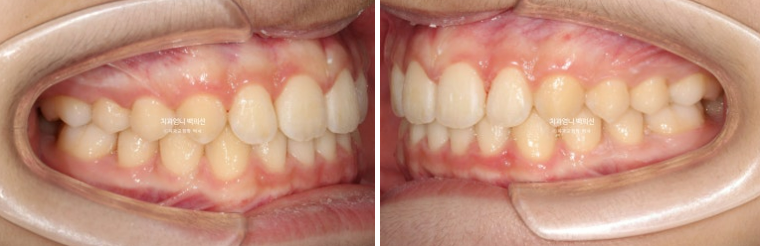

24.03~25.05

24.03

작년 봄, 교정치료를 위해 내원한 만 10세 어린이입니다.

위 앞니가 아랫니를 많이 덮어 깊게 물리는 과개교합이 보입니다.

위 앞니 돌출이 보입니다.

남아있는 유치 두 개가 가위교합입니다.

첫세트의 장치는 22개가 나왔습니다. 24년 3월부터 24년 9월까지 첫세트의 장치를 모두 낀 후 모습입니다.

24.09

앞니 돌출은 해결이 되었으나 앞니가 깊게 물리는 과개교합이 남아있습니다.